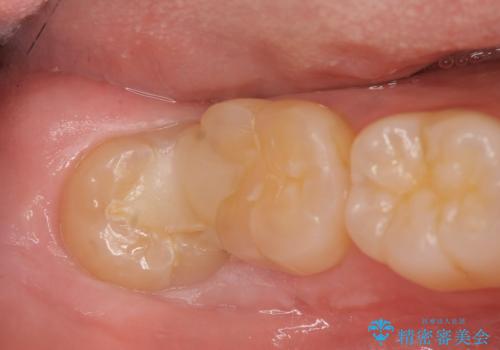

親知らずを起因とする虫歯治療

- 右下奥の強烈な痛み、腫れの改善を求めて来院されました。

視診・X線写真より親知らず周囲の進行した炎症発生、倒れた親知らずに起因する歯の神経に達する深い虫歯が見られました。

親知らずは抜去を行い、手前の第2大臼歯は根管治療後セラミッククラウンの製作を行います。